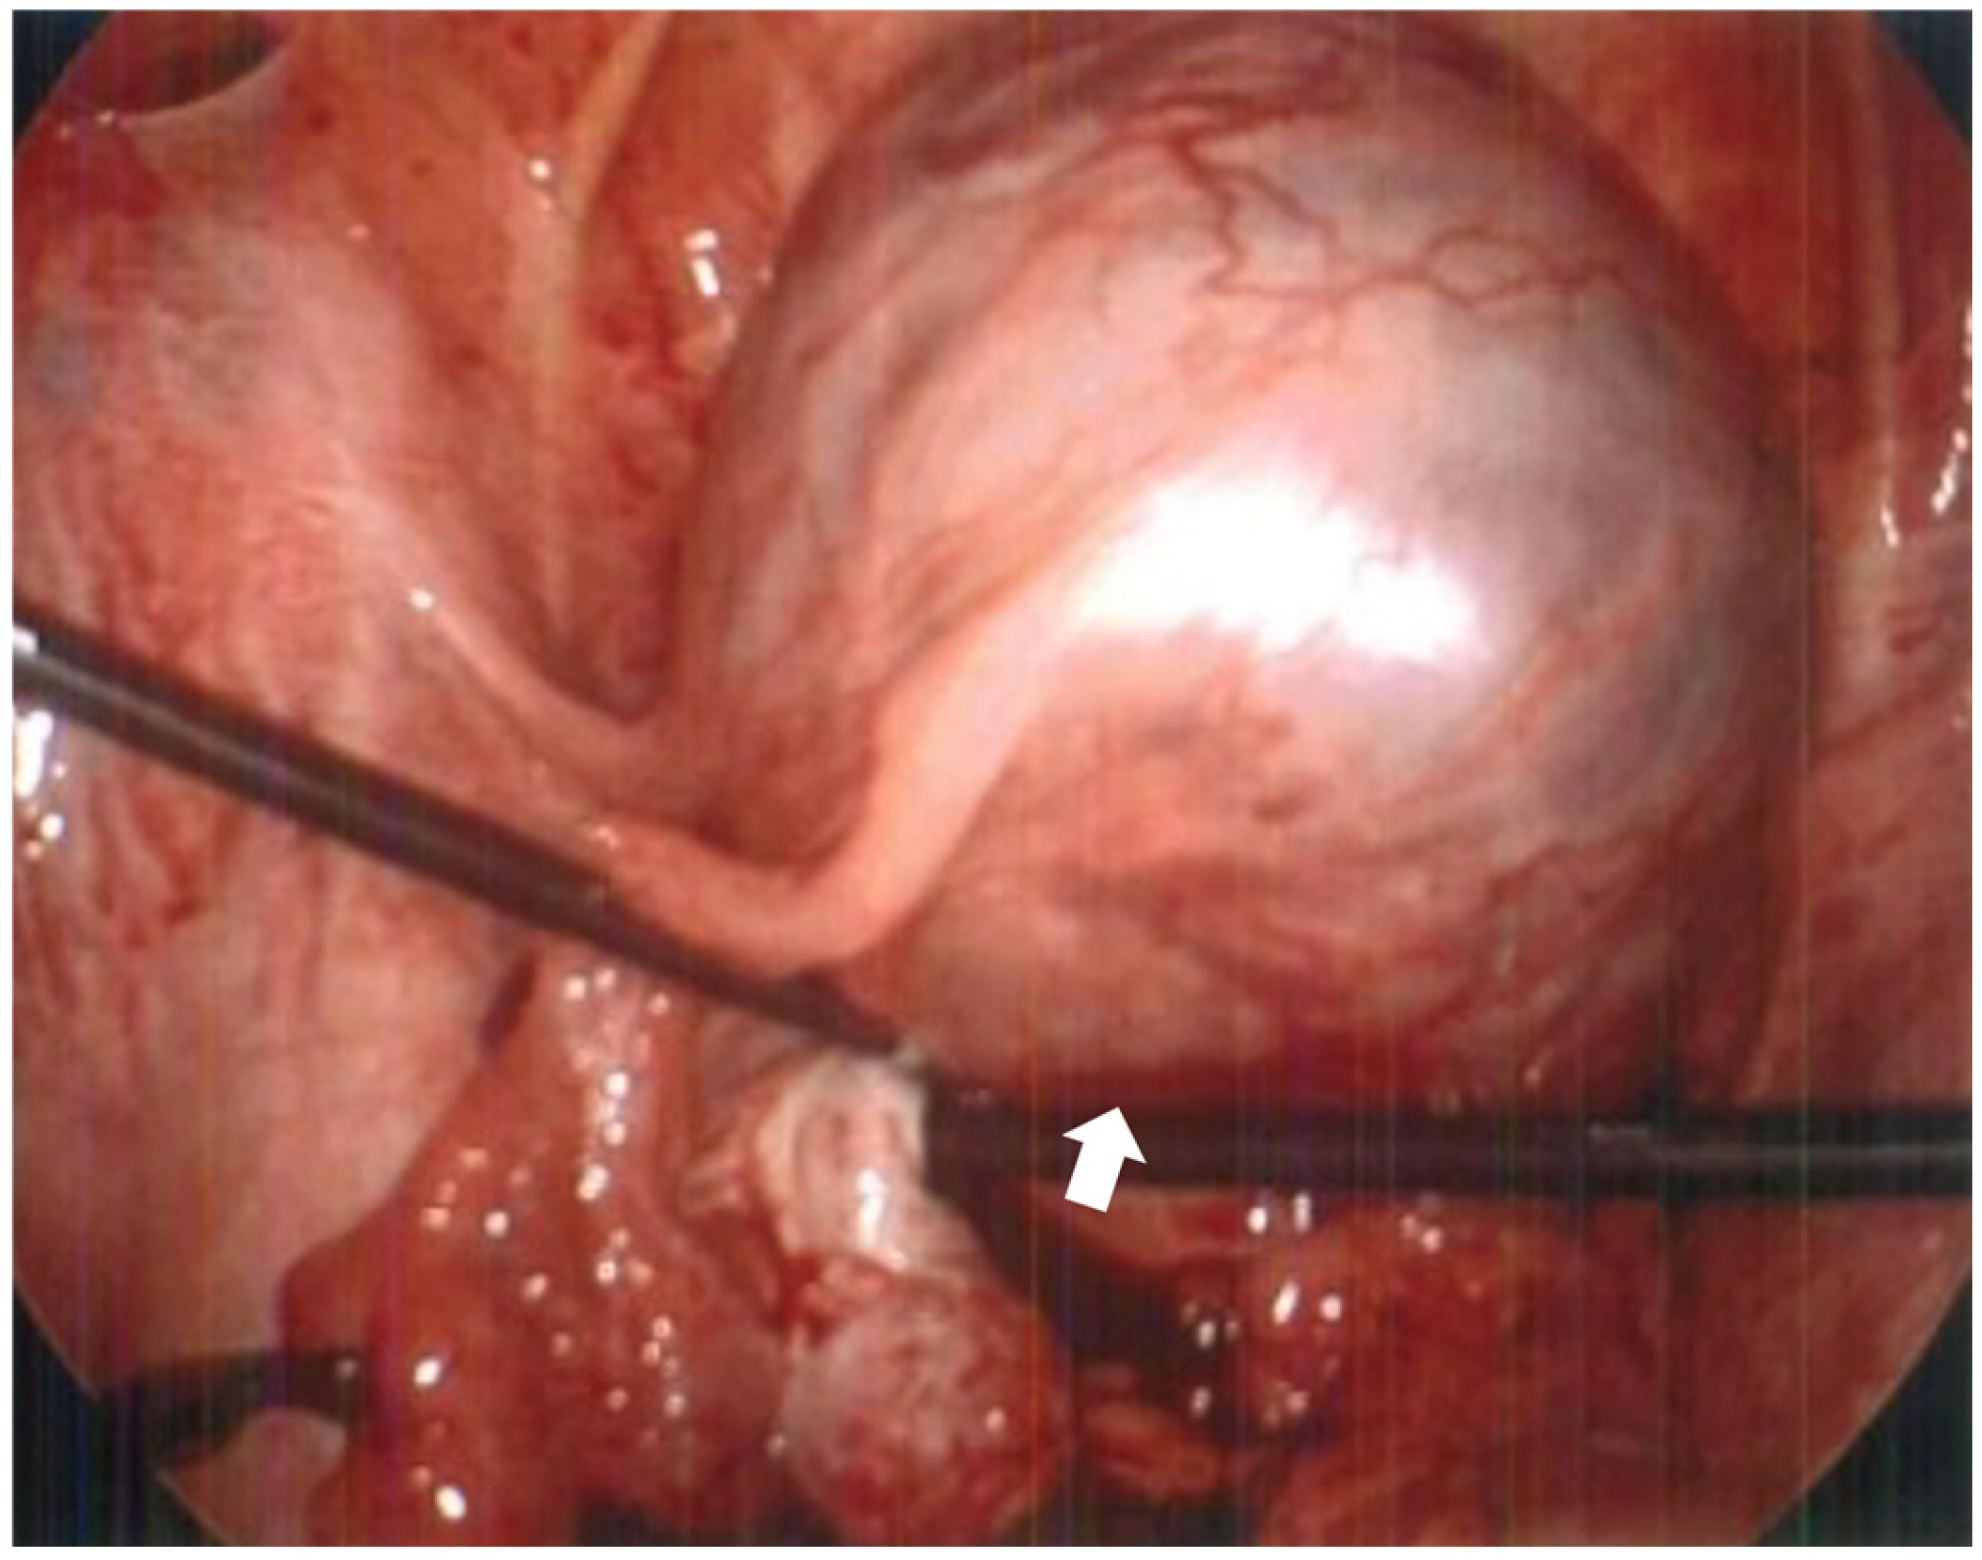

Figure 3.

Intraoperative photo taken during diagnostic laparoscopy demonstrating intact gestational sac within dilated portion of left fallopian tube. The gestational sac (arrow) is located primarily within the interstitial portion of the fallopian tube with no involvement of the distal end. There is increased musculature surrounding the fallopian tube which may represent extended myometrium from the uterine cornua.